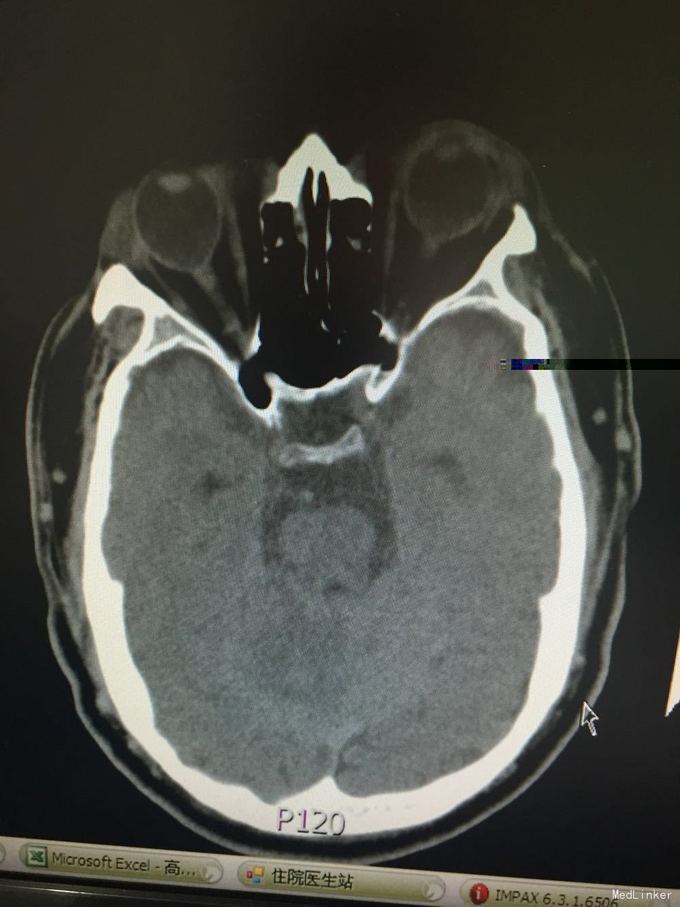

患者因突发意识不清3小时入院。既往脑梗死、高血压、糖尿病史,控制不佳。该患者于入院前3小时无明显诱因在工作中突发意识不清,起病时呼唤能回答,但口齿不清,伴右侧肢体无力,不能持物及行走,伴头痛,呕吐,呕吐物为胃内容物,测血压大于200mmHg,意识障碍快速进展加重,成昏睡状态,由120到我院,查头CT示:多发脑梗死。

1脑梗死 2肺炎 3高血压3级 4.2型糖尿病 患者行动脉溶栓术,手术顺利,术后安返病房,查体:血压170/89 轻度嗜睡状态,言语笨拙,查体合作,双侧瞳孔等大同圆,对光反射存在,双眼轻度左侧凝视受限,鼻唇沟对称,伸舌居中,右上肢肌力4级,右下肢制动,左侧肢体肌力5级,右侧肌张力减低。病理征阳性,处置:动态监护,右下肢制动24小时,改善循环、神经保护、改善脑灌注、抗炎、化痰补液 对症支持治疗。